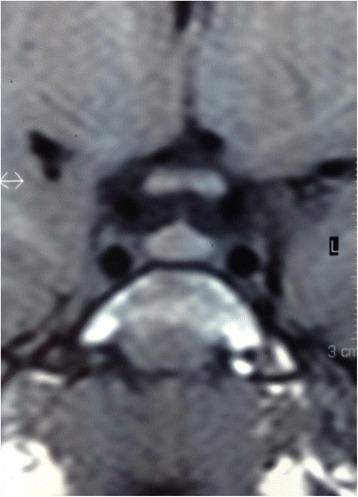

Rapid-onset obesity with hypoventilation, hypothalamic dysfunction, and autonomic dysregulation syndrome is a rare pediatric disorder with a variable sequence of clinical presentations, undefined etiology, and high risk of mortality. Our patient presented an unusual course of the disease accompanied by a homogenous mild enlargement of her pituitary gland with an intact pituitary-endocrine axis which, to the best of our knowledge, represents a new finding in rapid-onset obesity with hypoventilation, hypothalamic dysfunction, and autonomic dysregulation syndrome.

We present a documented case of a 4 years and 8-month-old Syrian Arabic girl with a distinctive course of signs and symptoms of rapid-onset obesity with hypoventilation, hypothalamic dysfunction, and autonomic dysregulation syndrome accompanied by mature ganglioneuroma in her chest, a homogenous mild enlargement of her pituitary gland, generalized cortical brain atrophy, and seizures. Three months after her first marked symptoms were noted she had a sudden progression of severe respiratory distress that ended with her death.

快速进展性肥胖伴通气不足、下丘脑功能障碍和自主神经调节异常综合征是一种罕见的儿科疾病,临床表现多样,病因不明,死亡率高。我们的患者呈现出该病的不寻常病程,伴有垂体均匀轻度增大且垂体 - 内分泌轴完整,据我们所知,这在快速进展性肥胖伴通气不足、下丘脑功能障碍和自主神经调节异常综合征中是一项新发现。

我们报告一例4岁8个月大的叙利亚阿拉伯女孩,患有快速进展性肥胖伴通气不足、下丘脑功能障碍和自主神经调节异常综合征,有独特的症状和体征,同时胸部伴有成熟的神经节神经瘤、垂体均匀轻度增大、广泛性皮质脑萎缩和癫痫发作。在首次出现明显症状三个月后,她突然出现严重呼吸窘迫并最终死亡。